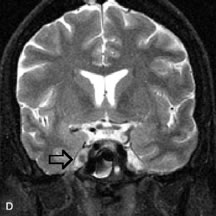

Lymphomas have MRI characteristics similar to those of inflammatory lesions in that they are hypointense to fat and isointense to muscle on T1-weighted images (Fig. 22). They may appear hyperintense to fat on T2-weighted images, perhaps owing to less fibrosis than that seen in orbital inflammatory pseudotumor, although this is not a consistent finding.31,50,66 Lymphoid tumors typically enhance moderately after contrast injection. Unfortunately, studies have shown that tumor density and homogeneity are similar between inflammatory and malignant orbital infiltrates, and MRI cannot differentiate these lesions.72,73

Fig. 22. A and B. T1- and (C) T2-weighted MR scans demonstrate a poorly defined multicompartmental mass enveloping the lateral rectus, superior rectus, and levator palpebrac superioris muscles. The lesion is isointense to brain on T1- and T2-weighted scans, as is typical for highly cellular neoplasms. D. Postcontrast fat-suppressed T1-weighted scan demonstrates intense enhancement of the infiltrating intraconal and extraconal tumor.